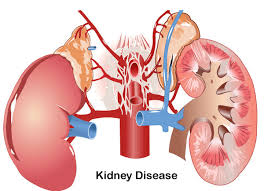

اکثر بیماریهای کلیوی به نفرونها حمله میکنند. این آسیب گاهی باعث میشود که کلیهها دیگر نتوانند مواد زائد را از بدن خارج کنند. از علل بروز بیماریهای کلیه میتوان به مشکلات ژنتیکی، صدمه دیدن یا مصرف دارو اشاره کرد. ابتلا به دیابت، فشار خون بالا یا ابتلا یکی از خویشاوندان نزدیک به بیماری کلیوی احتمال بروز ناراحتی کلیه را افزایش میدهد. بیماری مزمن کلیه و نارسایی کلیه به آهستگی و ظرف چندین سال به نفرونها آسیب میزند. دیگر ناراحتیهای کلیه عبارتاند از:

بیماری کلیه چیست؟

بیماریهای کلیوی به اختلالهایی گفته میشود که به کلیهها یعنی دو اندامی آسیب میزند که هورمونهای معینی را تولید میکنند و میزان مواد شیمیایی را در خون تنظیم میکنند.

ناراحتی کلیه معمولاً هر دو کلیه را درگیر میکند. اگر بیماری توانایی کلیه را در دفع و تنظیم آب و مواد شیمیایی مختل کند، مایع اضافی و مواد زائد در بدن جمع میشود و علایم و ورم شدید اورمی (نارسایی کلیه) بروز مییابد. بیماری کلیه انواع و علل متفاوتی دارد که میتوان آنها را به سه دسته ارثی، مادرزادی یا اکتسابی تقسیم کرد.